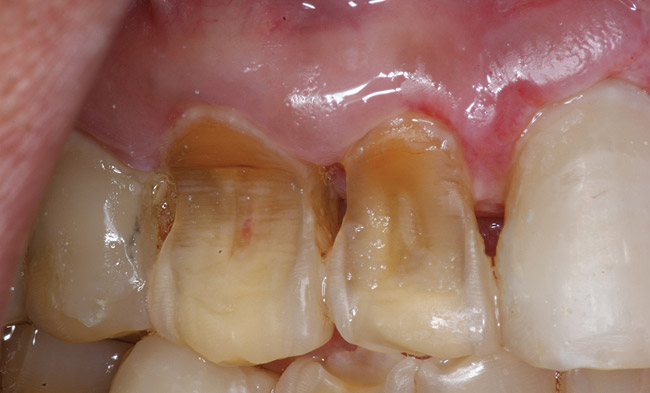

If a patient has risk factors that can contribute to dental erosion, an examination will reveal clinical signs and symptoms of dental erosion. It is unlikely that dental erosion will be seen without other contributing factors. Tooth wear and abrasion typically occur in combination with dental erosion. In the clinical evaluation of tooth surfaces for the diagnosis of erosion, what is typically seen are smooth, shiny surfaces of the teeth where the usual anatomic form of the tooth should be. In patients ingesting very acidic diets, the facial surfaces of anterior teeth are very smooth, and if the beverages being ingested have high sugar content, these teeth may have caries at their facial gingival margins (Figure 1). The occlusal surfaces of posterior teeth in the more advanced stages of erosion due to regurgitation may have extensive exposed dentinal areas with loss of anatomic form (Figure 2). In some cases, the chemical erosion combined with toothbrush–toothpaste abrasion can remove all the enamel, leaving only the dentin exposed (Figure 3). These teeth may exhibit sensitivity. Posterior teeth with restorations may demonstrate fillings that are higher than the surrounding occlusal surfaces of the enamel. Anterior teeth may demonstrate more incisal translucency due to tooth loss at the incisal edge. In patients with the eating disorder bulimia nervosa, who vomit, the hydrochloric acid causes extensive damage to the lingual surfaces of the anterior teeth, where the enamel is lost, leaving exposed dentin (Figure 4).

Figure 3  In a patient who smoked a pipe, the nicotinic acid causing tooth erosion was accentuated by the use of a highly abrasive smoker’s toothpaste. Some of the teeth have been restored with bonded composite resin.

Figure 3